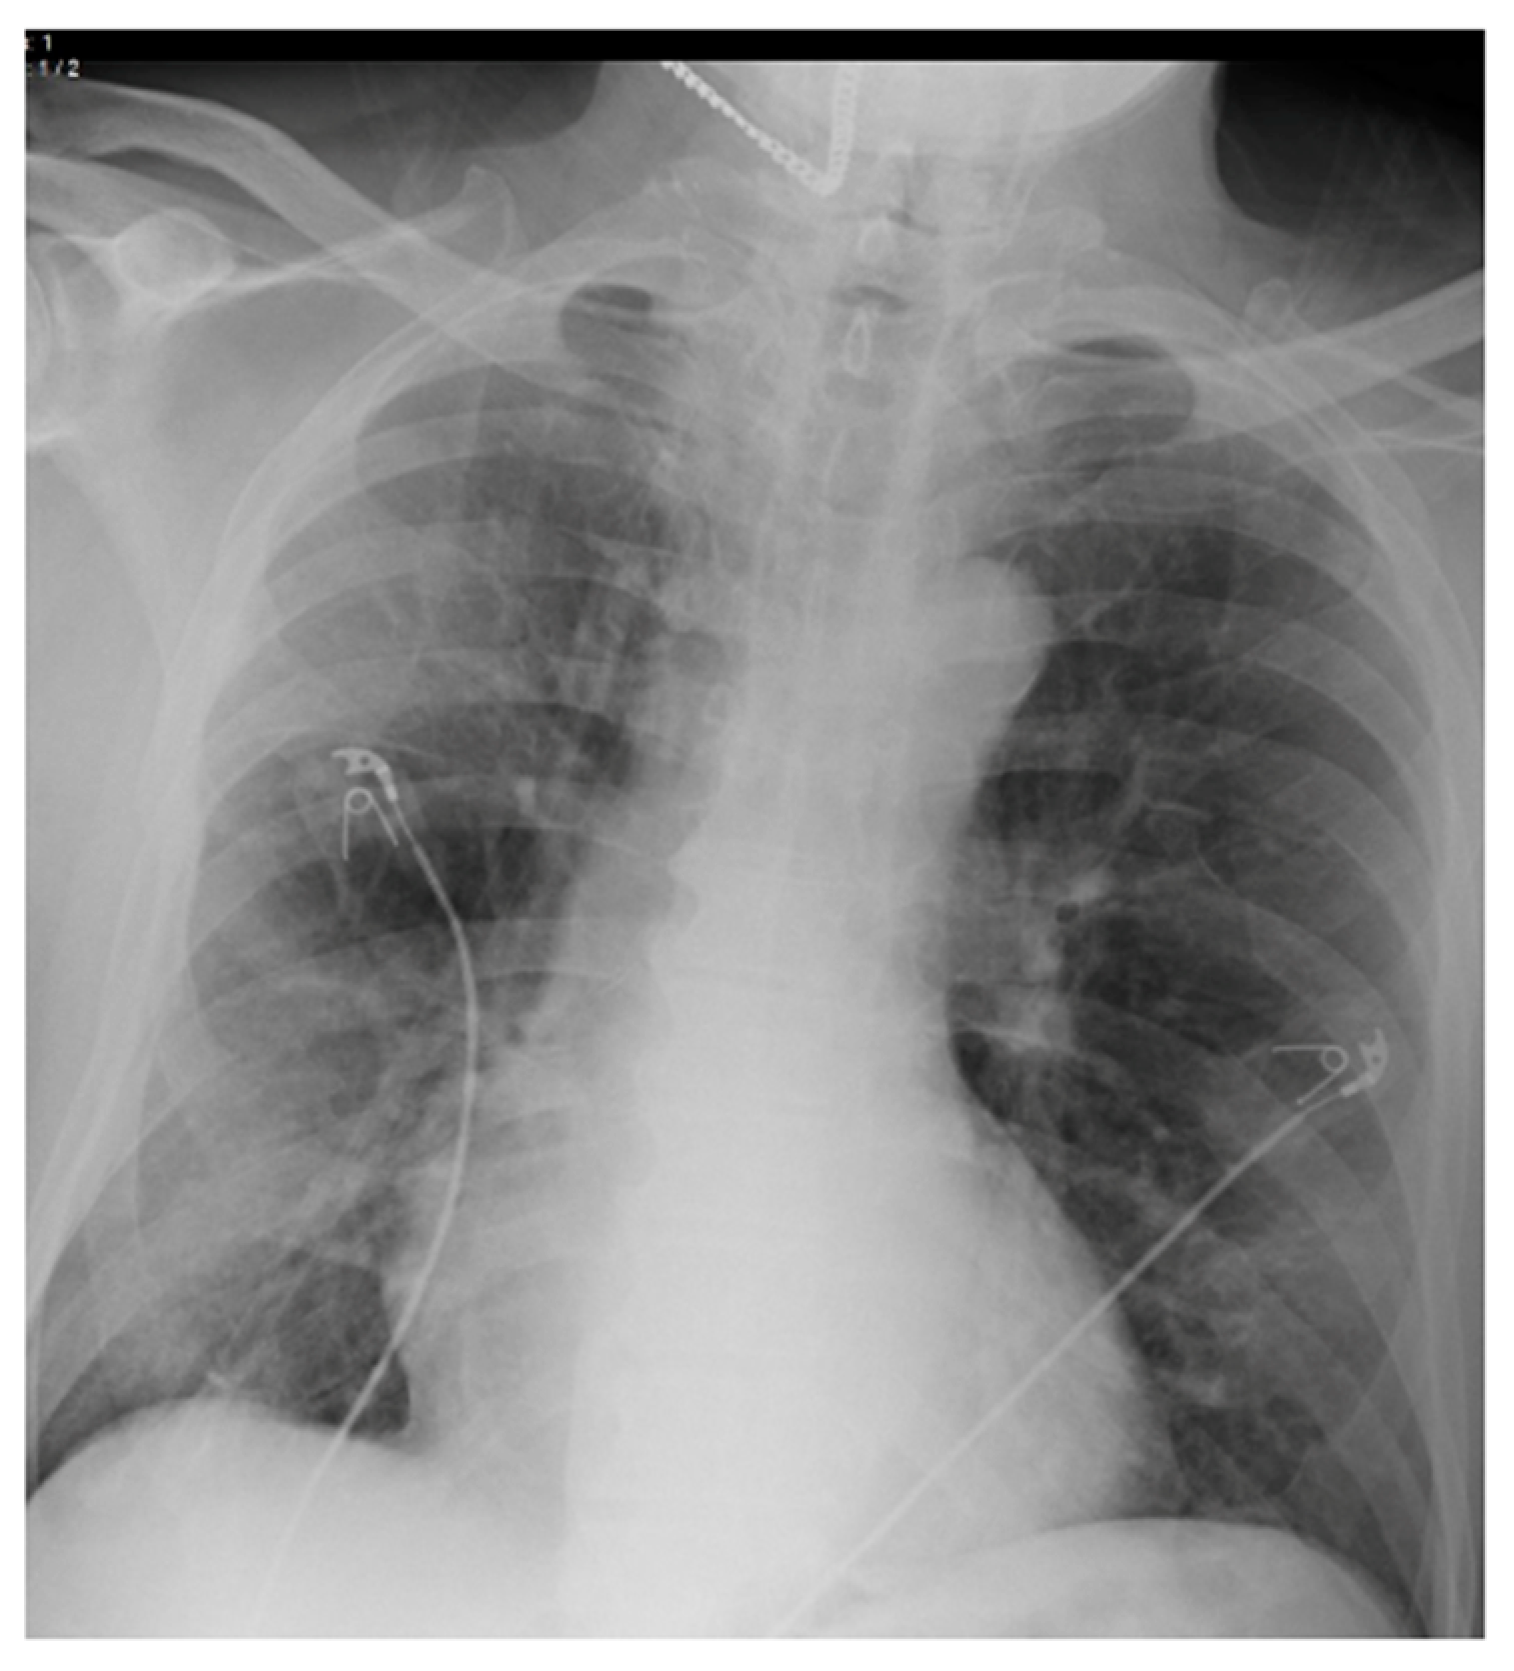

2.3. Imaging and Analysis